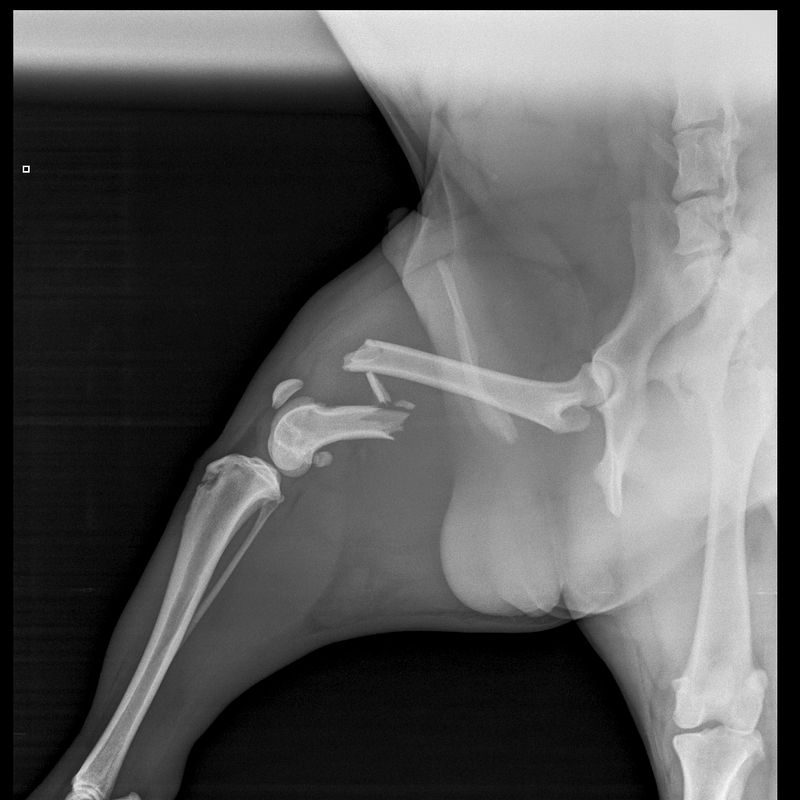

SPCA Inspectors visited the defendant and he provided false information about Rocka, telling them that he had euthanised him. He eventually admitted that Rocka was in his vehicle, injured and had not received veterinary treatment. Inspectors saw that Rocka’s right hind leg was obviously and extremely swollen, and Rocka wasn’t placing weight on it. Rocka was surrendered into the care of SPCA.

The veterinarian who examined Rocka confirmed a broken femur and said he would have suffered severe pain at the time of the fracture, up until he was treated by a vet. Unfortunately, due to the extent of his injuries, Rocka was euthanised.